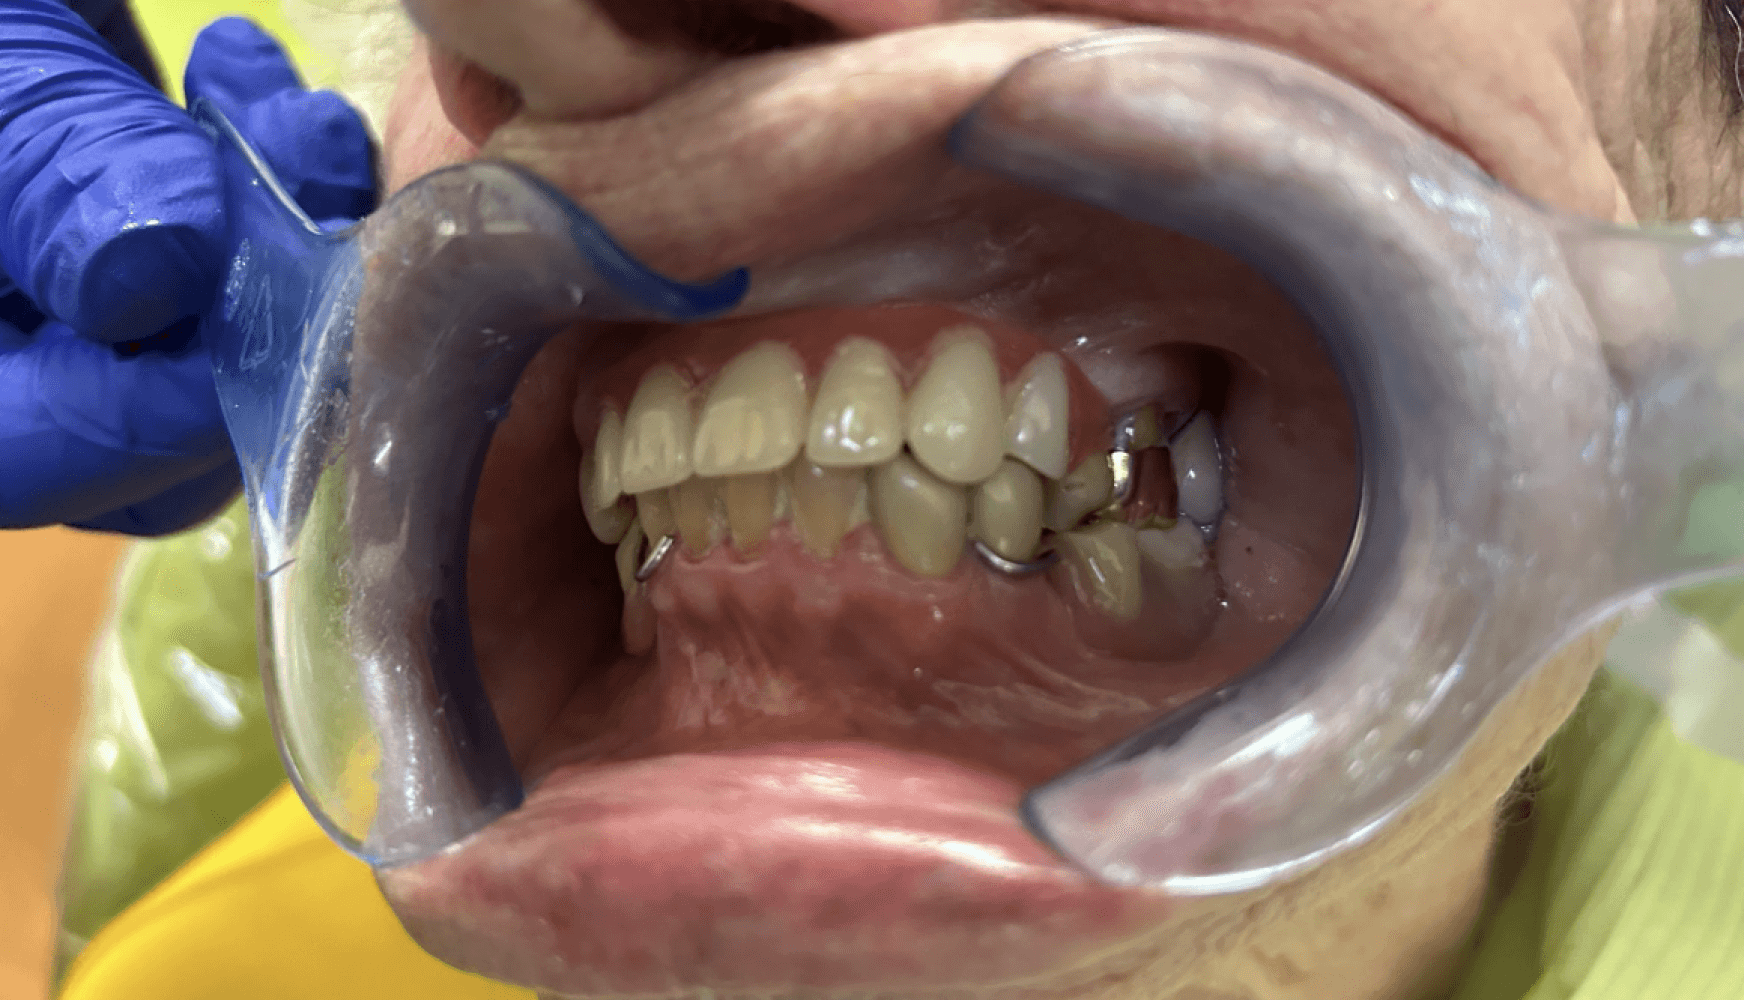

Figures 5a, 5b, 5c:

Figure 5a, 5b, 5c: The maxillary partial denture seated in the patient’s mouth.